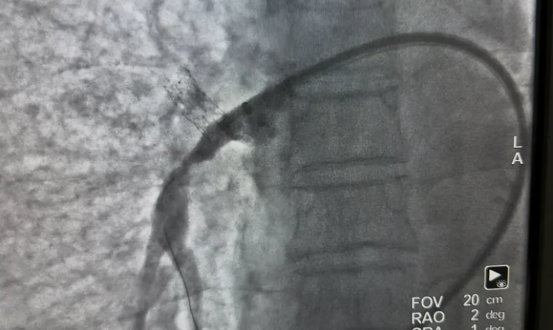

面对这一药物治疗效果有限、外科手术风险高的疾病,医疗团队制定了“微创、安全、有效” 的介入治疗方案。通过分次实施肺动脉成形术,逐步解除肺动脉狭窄,降低肺动脉压力。

疗效立竿见影。首次术后三天,张先生自觉气喘、胸闷明显缓解,阵发性干咳亦可耐受,肺动脉压降至66mmHg。完成三次手术后,他的肺动脉压已接近正常水平(40mmHg),日常活动完全不受限制,生活质量显著提升。